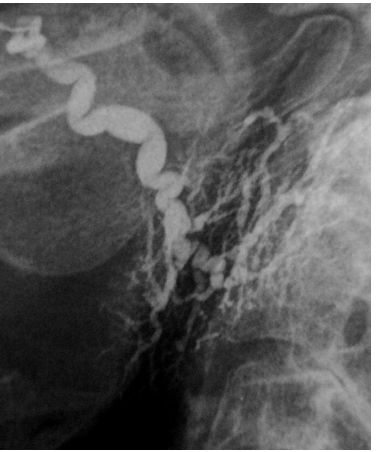

70.下列那一唾液腺攝影圖像可以診斷為涎腺管炎(sialodochitis) ?(A) (B) (C) (D)